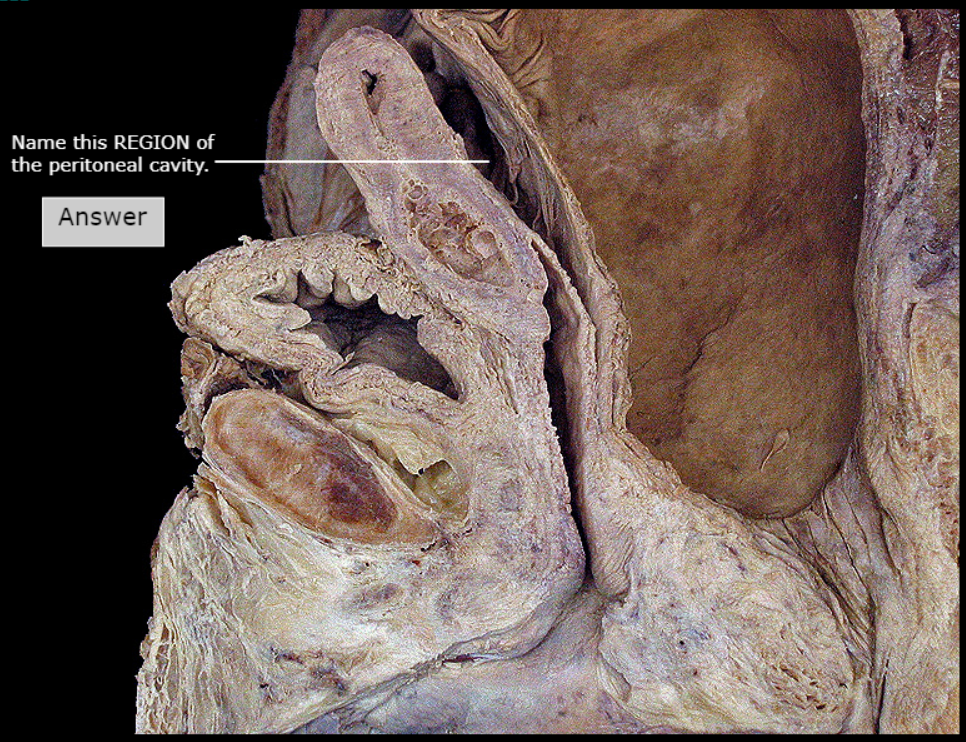

Rectouterine Pouch (Pouch of Douglas)

Posterior Fornix

Rectum

Ovary

Fundus of Uterus